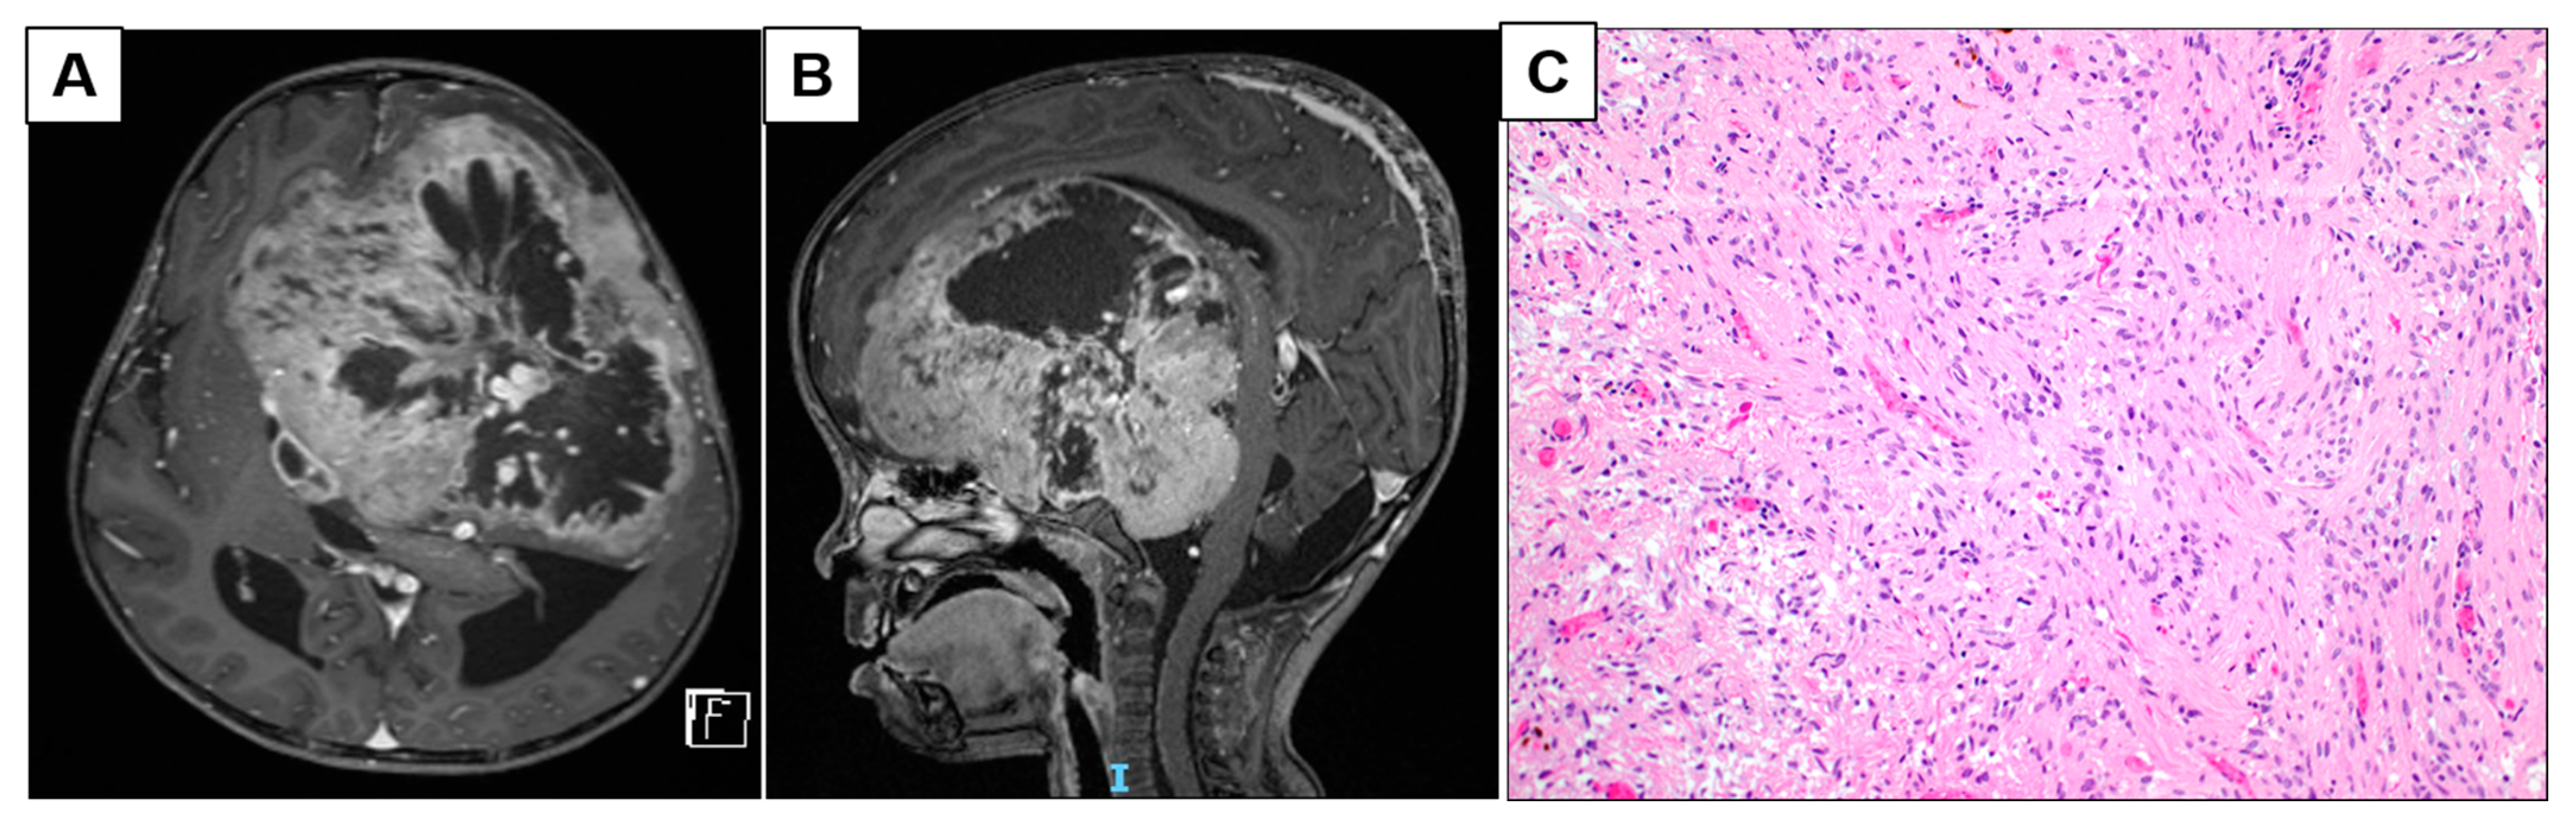

3.1.1. Patient 2: Large Frontotemporal PCA with Intratumoral Arterio-Venous Shunting